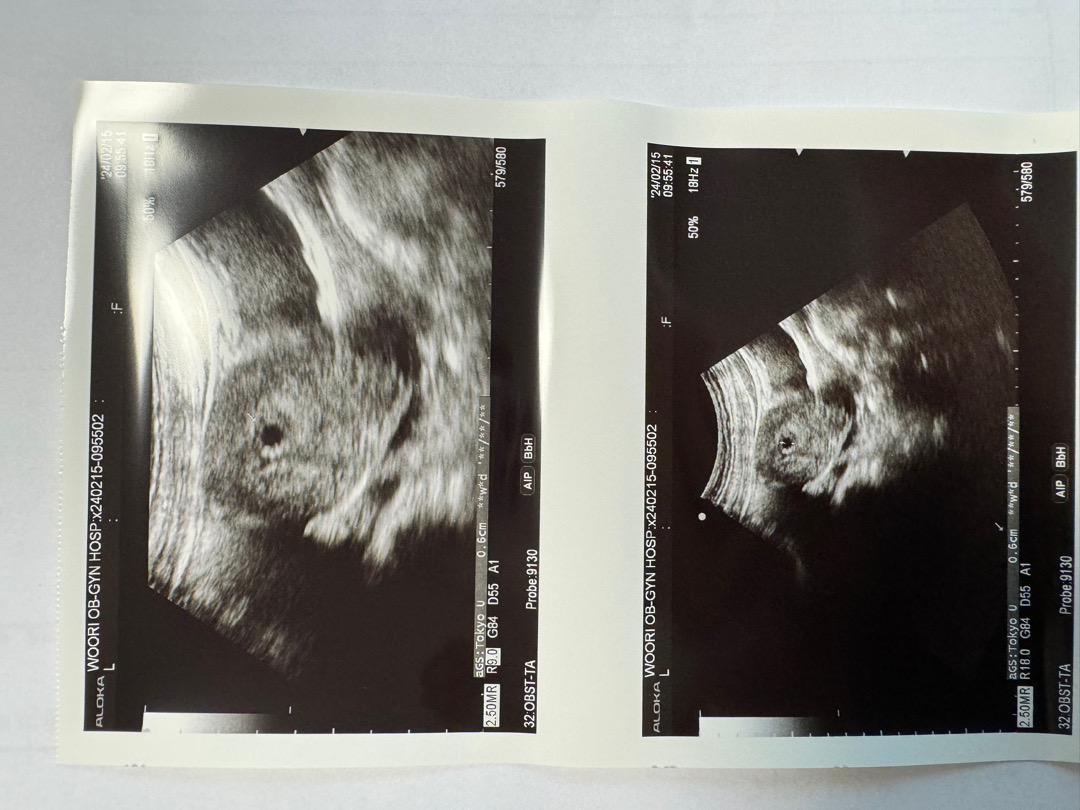

아기집이 두개 같아요!!

애기집확인❤️

임테기 역전으로 산부인고ㅏ 갔는뎅 애기집만보고왔오요^^! 첫째때보다 천천히 간건뎅ㅋㅋㅋ 그래도 아주 정가운데에 애기집을 예쁘게 만들었다네요❤️ 우리 뽀룡이 🦖❤️ 이주뒤엔 심장소리 들려줘❤️

두개요??????????오디요????????